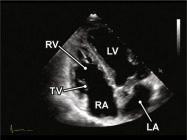

| 2.6. Mặt cắt trục dài cạnh ức qua buồng nhận thất phải |

||||||||

|

|

Cửa sổ siêu âm cạnh ức

Mặt cắt trục dài cạnh ức Ngả đầu dò xuống dưới hướng về phía đùi phải của bệnh nhân |

Nhĩ phải (RA) Van ba lá (TV) Thất phải (RV) |

|||||